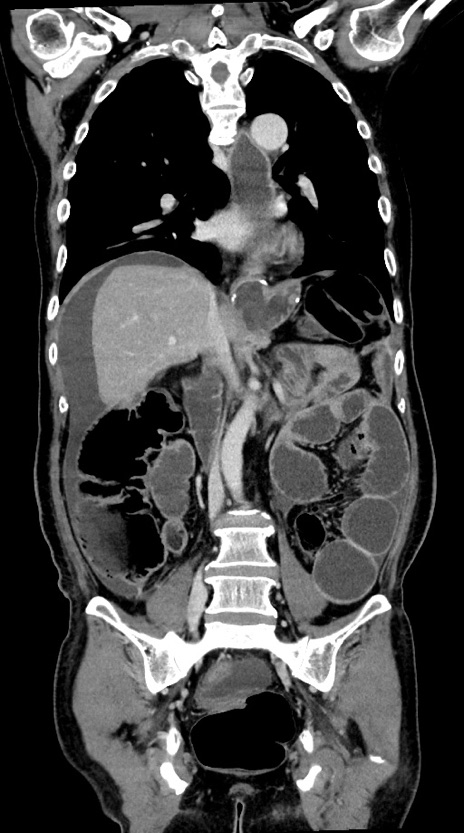

横断像

【症例】60歳代男性

【主訴】嘔吐

【現病歴】胃癌にて胃全摘後。食思不振が悪化し、夜中に嘔吐することがある。

【既往歴】胃癌、胃全摘、脾摘、胆摘後

【データ】WBC 5900、CRP 10.56